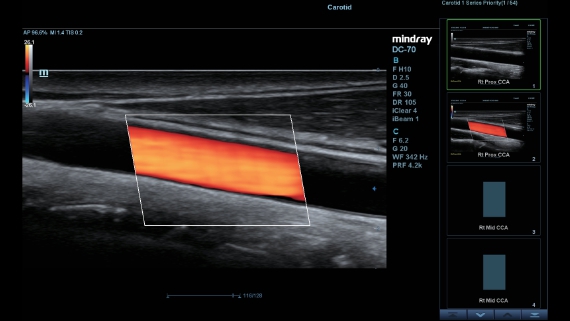

DC-60

AtenciĂłn dedicada para ECO

DescripciĂłn general

X-Insight es una soluciĂłn inteligente para un mejor diagnĂłstico.

La nueva soluciĂłn de Mindray representa una notable fusiĂłn de la informaciĂłn continua que recibimos de nuestros clientes respecto de sus necesidades clĂnicas con las tecnologĂas de ecografĂa de vanguardia en constante evoluciĂłn. Llena de vitalidad, con el objetivo de comprender el futuro y llegar al infinito, Mindray mejora constantemente con una mayor escalabilidad.

Como colaborador versĂĄtil, DC-60?ECHO con X-Insight tiene por objetivo proporcionar una soluciĂłn integral para ayudarlo a administrar todos los aspectos de la prĂĄctica clĂnica diaria con facilidad y seguridad.

Sobre la base de un profundo conocimiento de las necesidades del cliente, el DC-60?ECHO con X-Insight estå dise?ado para brindar alta eficiencia con imågenes precisas, lo que se ve potenciado con eXpress Clarity (claridad exprés), eXceptional Intelligence (inteligencia excepcional) y eXceeding Experience (experiencia extraordinaria).